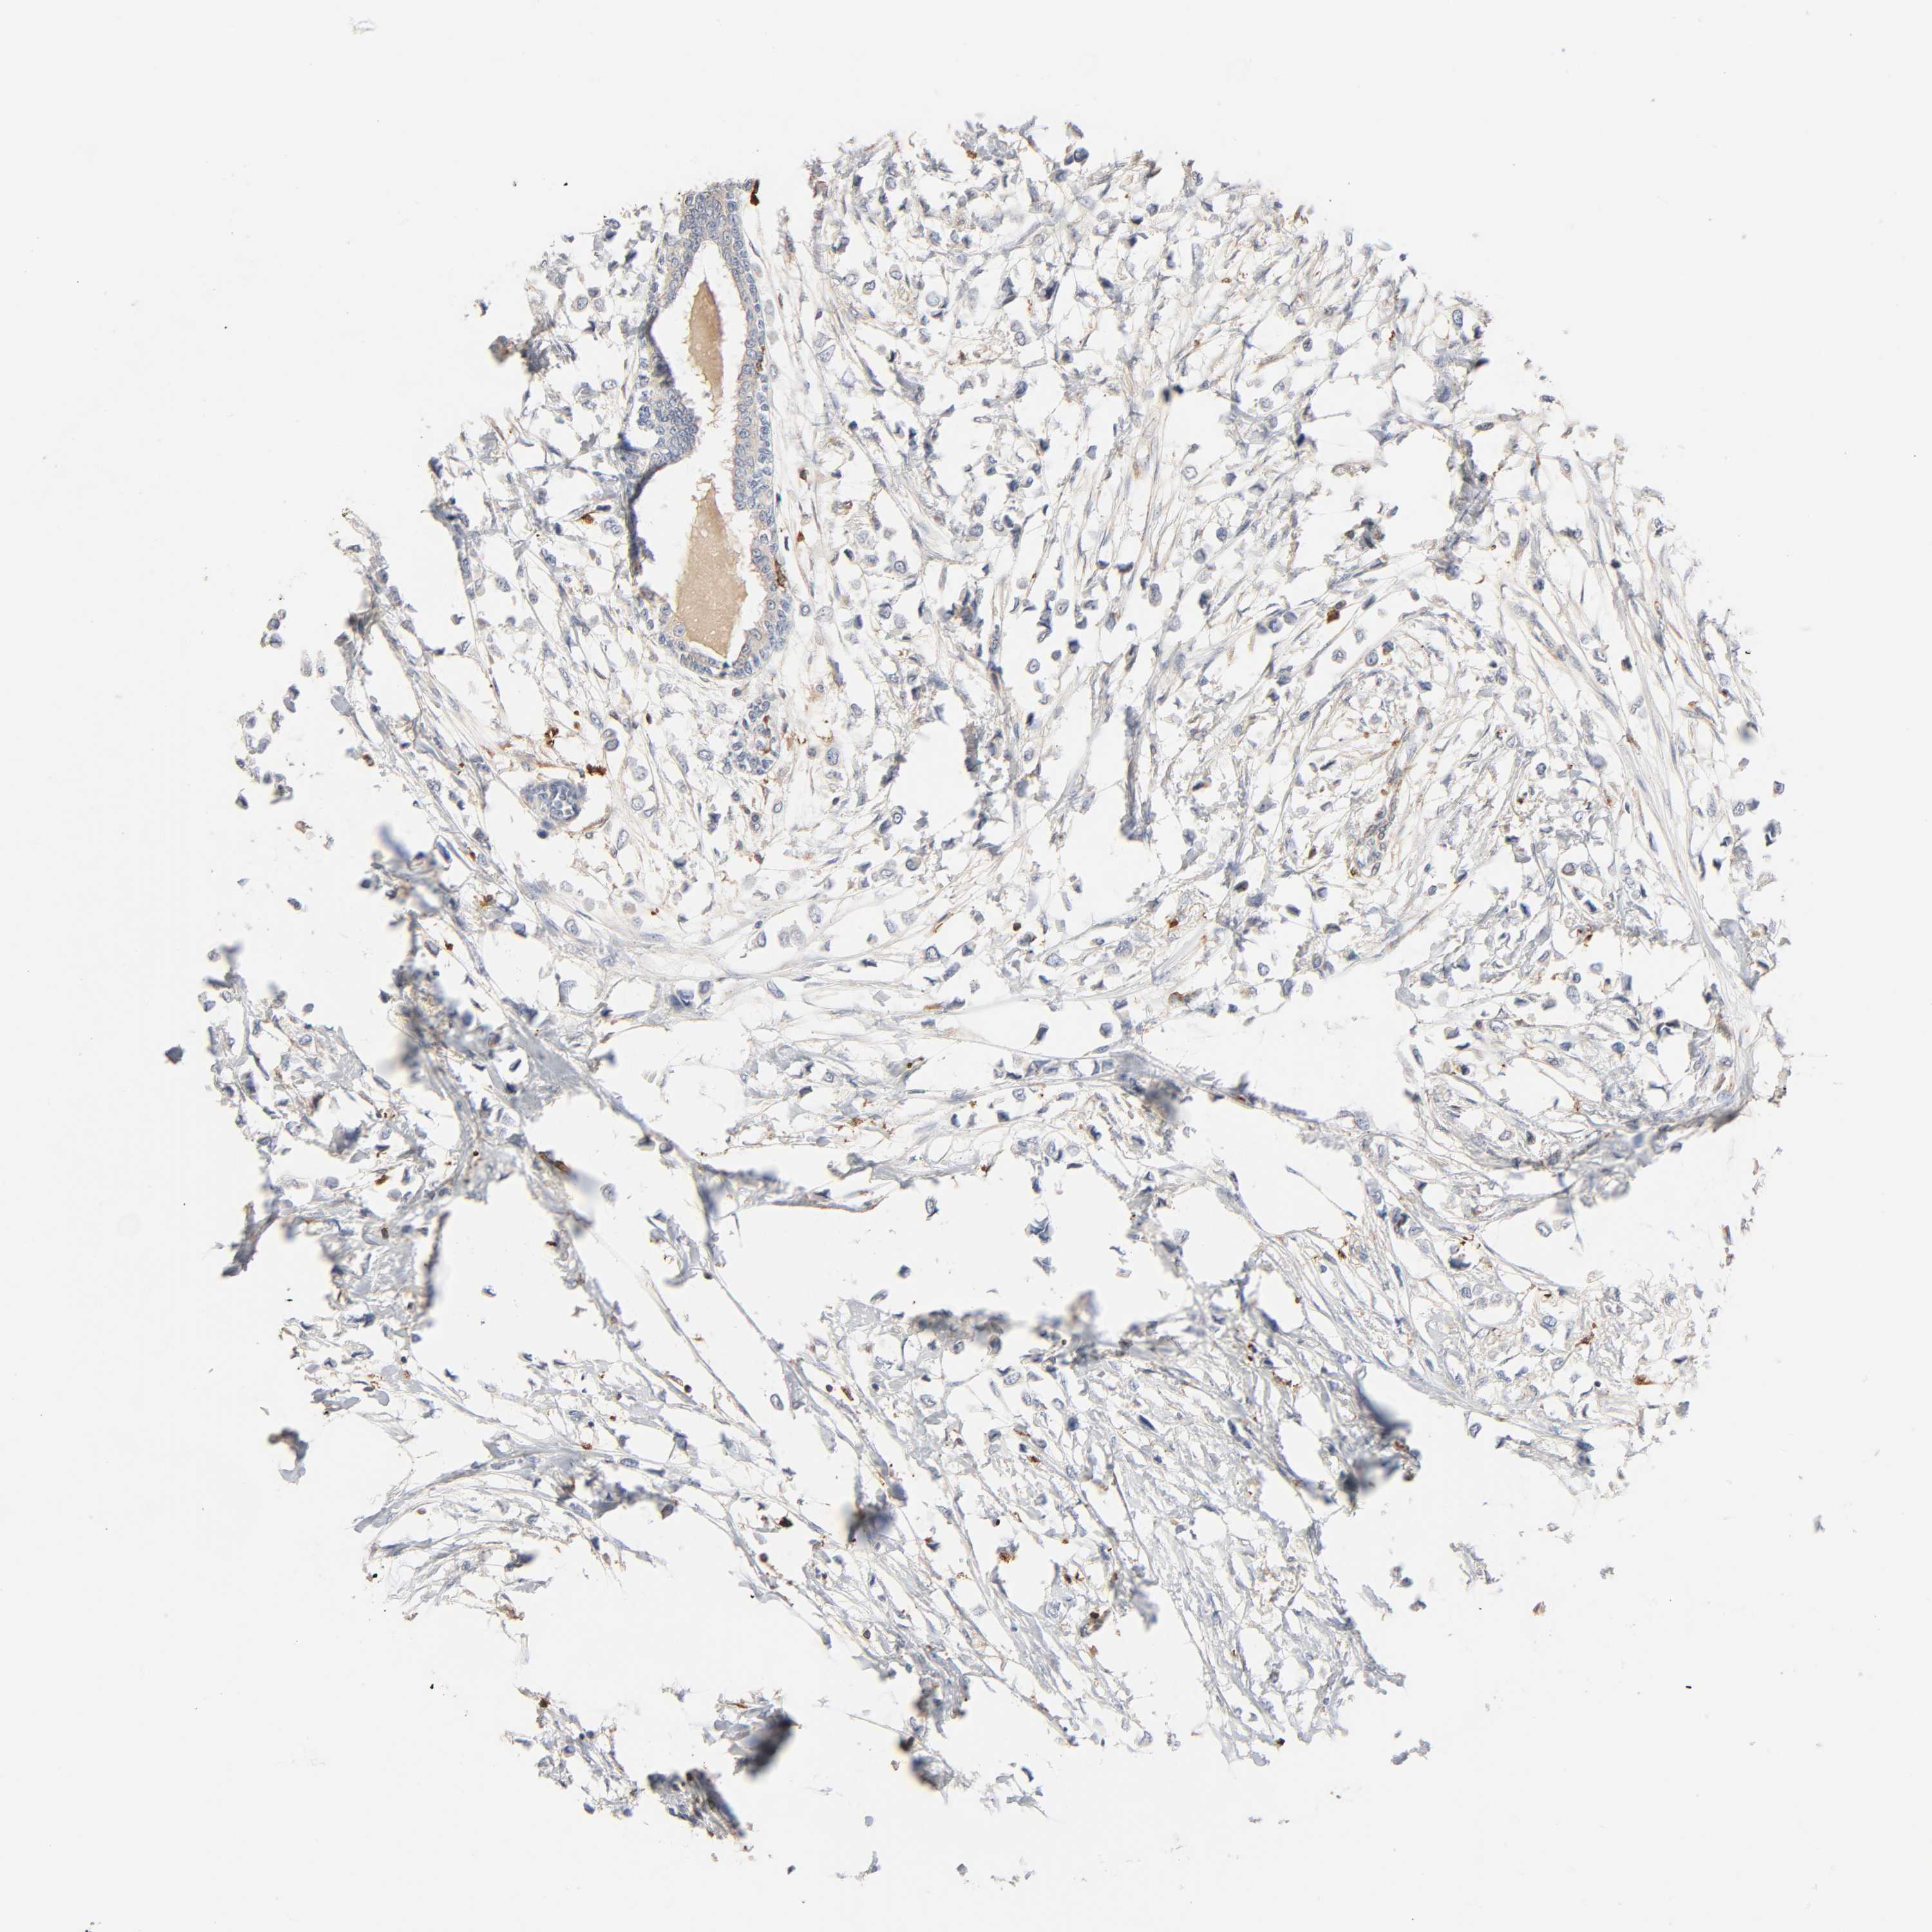

CANCER BREAST CANCER Show tissue menu

BRCA TCGA BRCA VALIDATION PROTEIN EXPRESSION